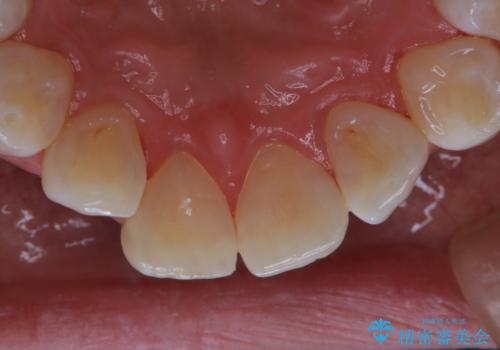

- 結婚式前にできる限りで白く、綺麗な歯にして欲しいとのことで来院されました。歯科は5.6年ぶりとのことでした。

PMTC60分コース(¥11000)とオフィスホワイトニング・エクセレントコース(¥29700)を行いました。

またPMTCを行うことで、ご自身本来の歯の色になり自然な明るさになります。

口元が自然な明るさになることで、より清潔感のある印象になるため結婚式・行事やイベント前などにもPMTCを行うはおすすめです。